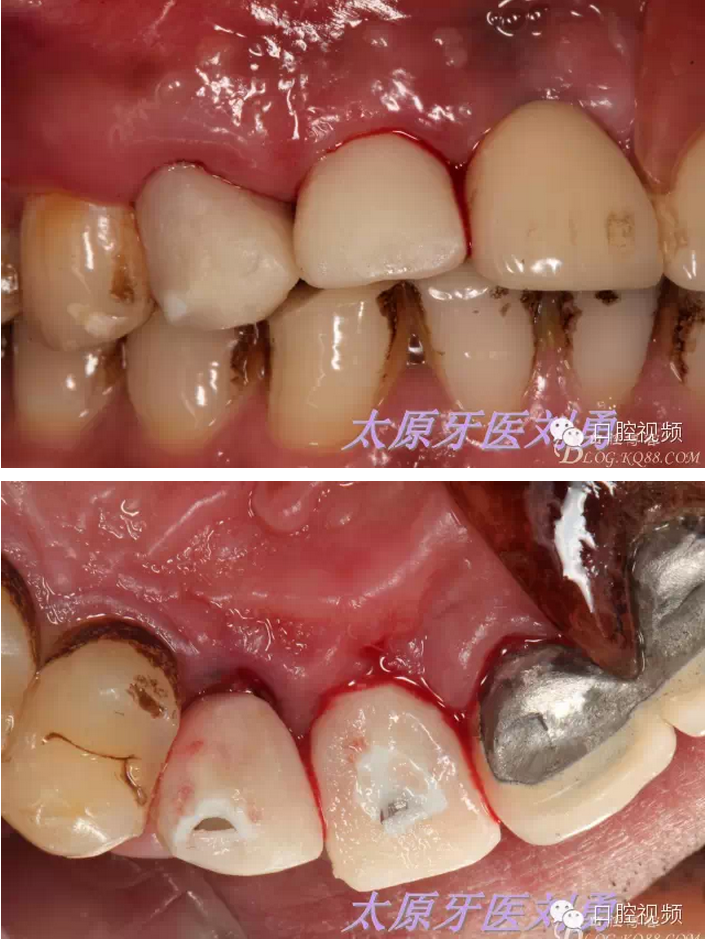

口內(nèi)檢查可見A23殘根,根面齲壞至齦下較深,局麻下,高速手機+加長金剛砂車針+球鉆,去除A23腭側(cè)牙根,保留唇側(cè)根壁,并修整,徹底刮治牙槽窩,沖洗后,偏腭側(cè)方向預(yù)備并植入種植體,種植體與唇側(cè)根壁之間隙植入biooss骨粉,初期穩(wěn)定性良好,上實心基臺,制作臨時冠引導(dǎo)牙齦成形。術(shù)后患者無水腫,且疼痛較輕。如下圖: